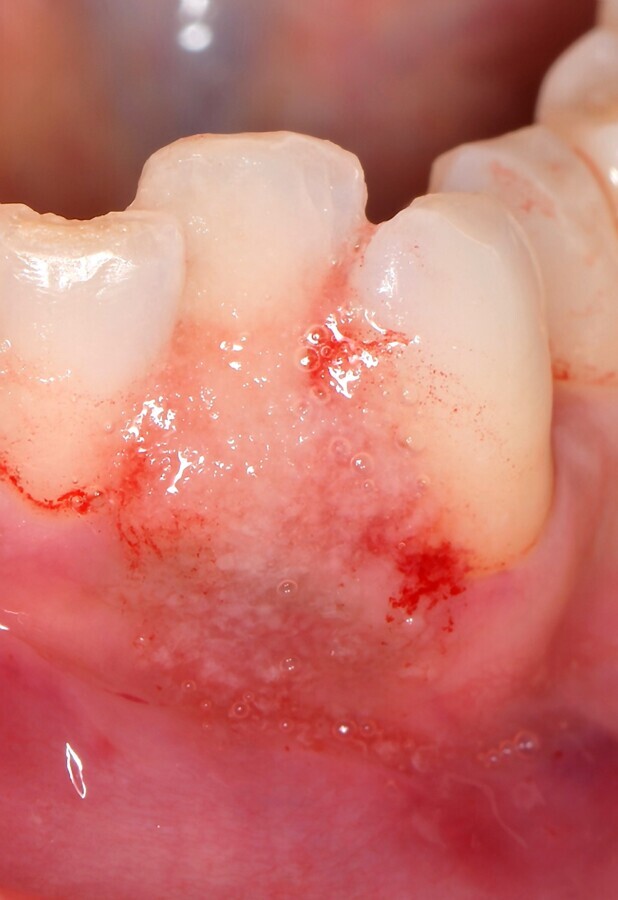

Figura 3. Vista frontal del defecto inicial. Los tejidos aparecen edematosos, la papila interdental está hinchada y despegada de las superficies de los dientes contiguos.